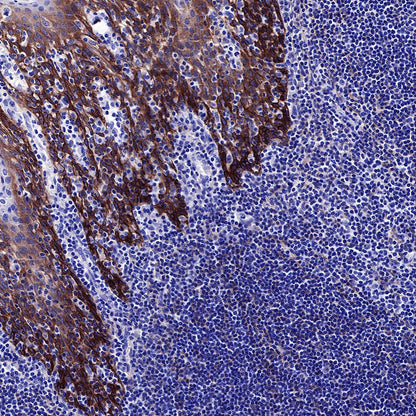

IHC shows positive staining in paraffin-embedded human tonsil. Anti-EGFR antibody was used at 1/2000 dilution, followed by a HRP Polymer for Mouse & Rabbit IgG (ready to use). Counterstained with hematoxylin. Heat mediated antigen retrieval with Tris/EDTA buffer pH9.0 was performed before commencing with IHC staining protocol.